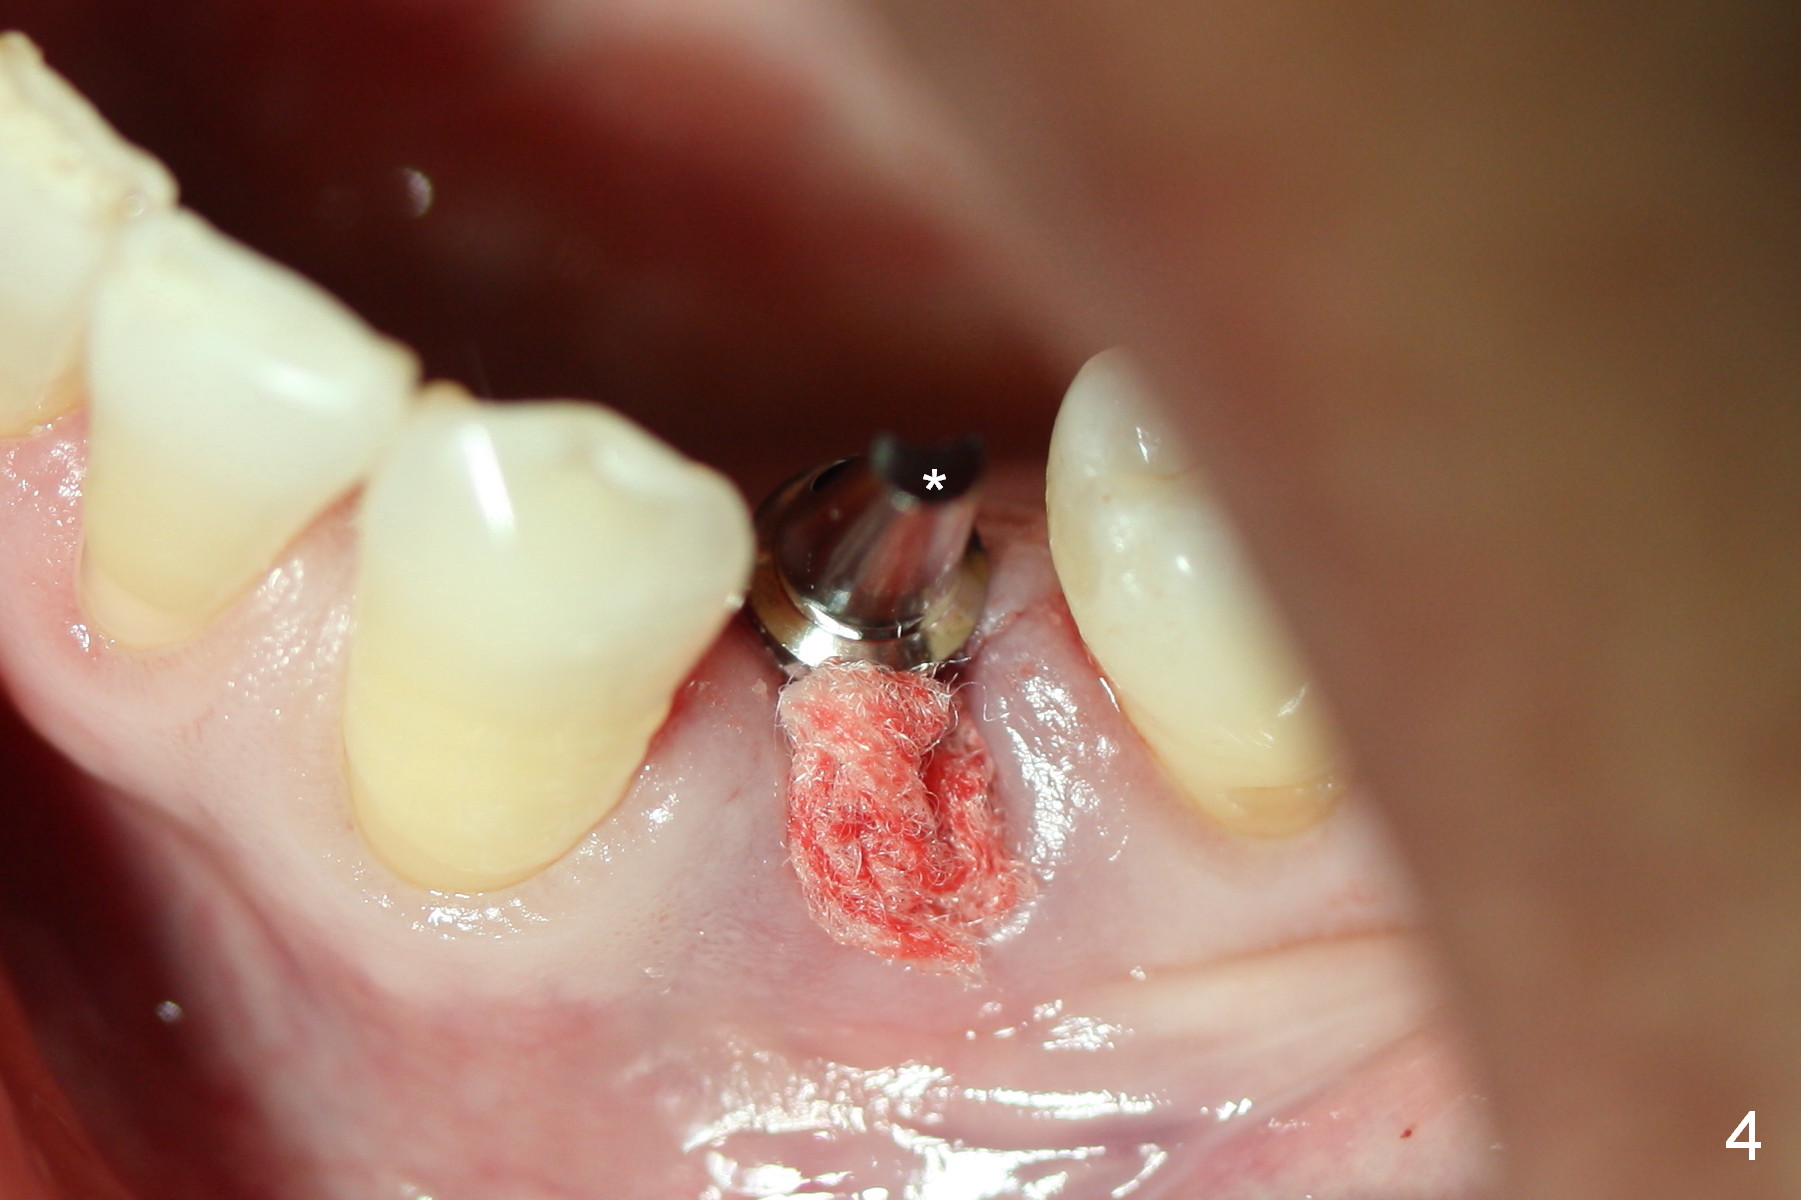

The residual root at #21 seems to be buccally positioned (Fig.1 *).  The initial osteotomy is established with the 1.6 mm drill at 11 mm (Fig.2).  Later the depth increases to 13 mm.  The initial osteotomy is found to be too lingual, but experience shows that as osteotomy increases in diameter, the trajectory would shift buccally due to the thick lingual plate (slope).  When 3.3 mm Magic drill reaches 11 mm, the patient feels pain.  It is probably due to the dense bone.  A 4x11 mm IBS implant cannot be seated due to high torque; it is removed.  The osteotomy is increased with 3.8 mm drill.  The implant is re-seated with >55 Ncm; it is over-lingually placed.  Due to failure to seat the implant driver completely, the implant cannot be un-torqued.  A 4.5 mm 15° angled abutment (3 mm cuff) is placed for immediate provisional (Fig.3,4 *).